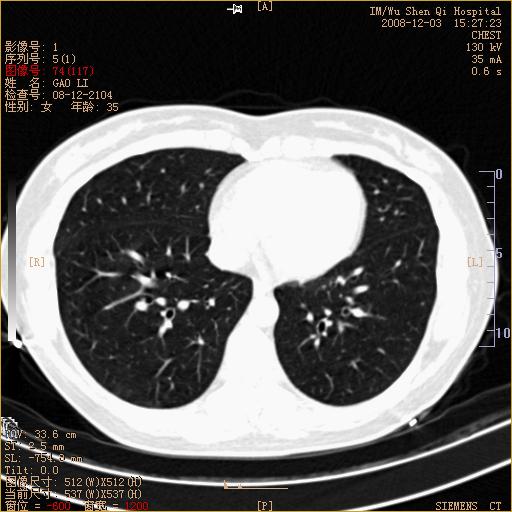

标题: CT16895:女,35岁,反复咳嗽数月,只传部分图像,是否考虑 [打印本页]

标题: CT16895:女,35岁,反复咳嗽数月,只传部分图像,是否考虑

左下肺支扩

典型“印戒征”。

印戒征,支持支扩.

左下肺扩支

印戒征,支扩